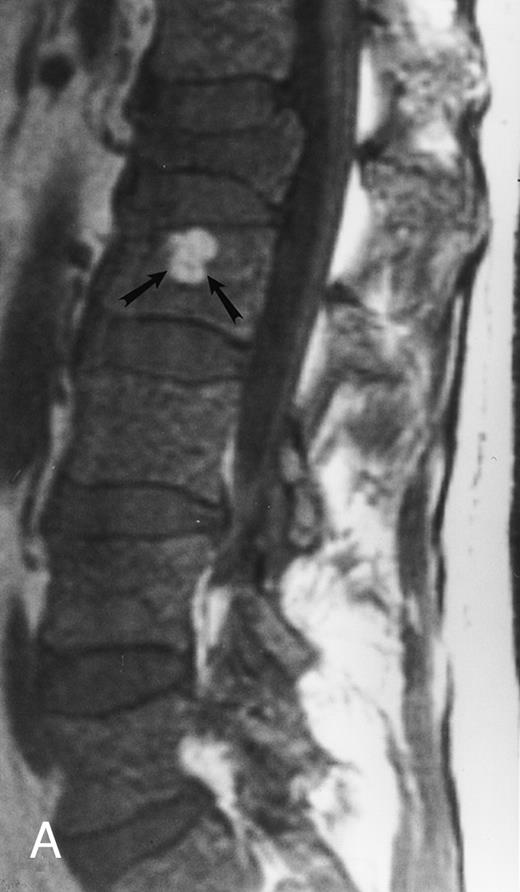

Variegated MR pattern of abnormal marrow in a 45-year-old man with multiple myeloma: T1-weighted (600/20, TR/TE) (A), relatively T2-weighted gradient recalled echo (650/20, TR/TE, flip angle 20°) (B), and enhanced T1-weighted (600/20, TR/TE ) (C) sagittal MR images of the lumbar spine show multiple tiny foci of marrow involvement. Arrows point to island of normal fatty marrow. Sagittal T1-weighted (600/20, TR/TE) MR image 6 months after initiation of chemotherapy (D) shows reappearance of fatty marrow in the spine. Note development of multiple vertebral collapses. T1-weighted MR image 1 year after bone marrow transplantation and total body irradiation (600/20, TR/TE) (E) shows resolution of marrow abnormality and homogeneous bright signal of fatty marrow in the lumbar spine. Note progression of compression fractures. Reprinted with permission from Moulopoulos et al.14,21